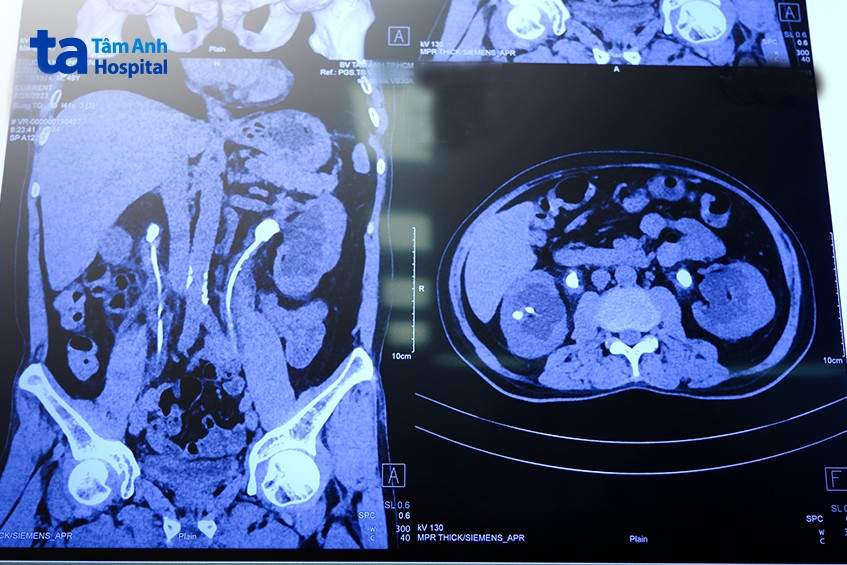

Kết quả chụp CT cho thấy người bệnh bị ứ nước 2 thận, nhiễm trùng tiểu, có ở thận trái và thận phải với kích thước: thận phải 2 viên kích thước 7mm và 10×18 mm, thận trái 2 viên kích thước 9mm và 13x21mm. Nếu không kịp thời điều trị có thể dẫn đến suy thận, ảnh hưởng đến sức khỏe và tuổi thọ của người bệnh.